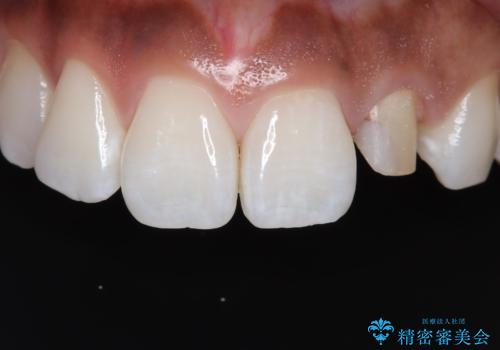

- 「前歯の歯の色が気になる」を主訴に来院された患者さんです。歯の大部分がプラスチックの材料で治療されていました。そこが劣化し変色していたためオールセラミッククラウンで治療を行いました。前歯の色を全体的に白くするために当院でオフィスホワイトニングも行いました。

左上2番の大部分がプラスチックの材料で治療されていました。そのプラスチックの材料が劣化して変色し虫歯になっている状態でした。なので古いプラスチックの材料を全て除去し、その下の虫歯を取った後、オールセラミッククラウンで治療を行いました。オールセラミッククラウンを装着する前に当院にてホワイトニングを行いました。